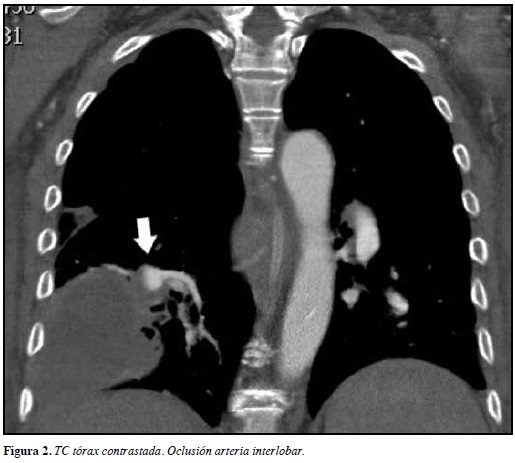

La TC de tórax contrastada demostró masa pulmonar cavitada (Figura 1) y oclusión de la arteria interlobar derecha (Figura 2), que confirmó el diagnóstico de infarto pulmonar.